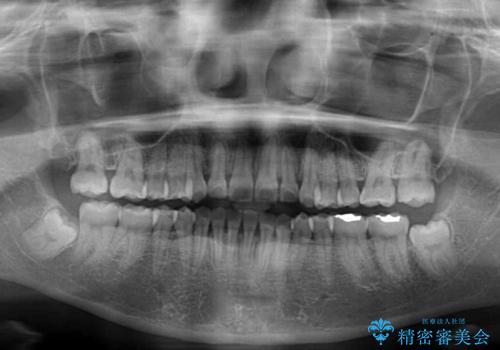

舌の突出癖により上下前歯が開咬となりましたが、舌のトレーニングと顎間ゴムの使用により、元々の被蓋関係に改善することができました。

アンカースクリューを用いて、出っ歯仕上がりを回避し、正中位置も改善することができました。